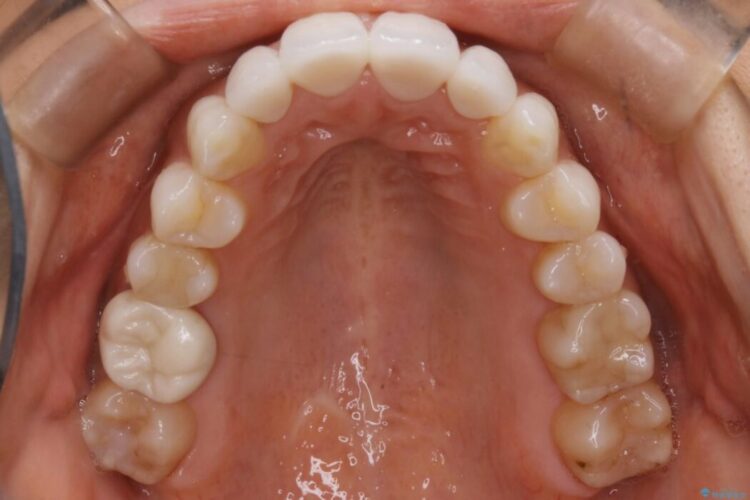

また確認したところ前歯と奥歯にセラミッククラウンで治療した歯があったため、そちらに影響のない範囲内で口腔内全体の噛み合わせが改善されるように歯を動かしていくことになりました。

既定のインビザラインの装着時間を守っていただけたこともあり整ったアーチとなりました。